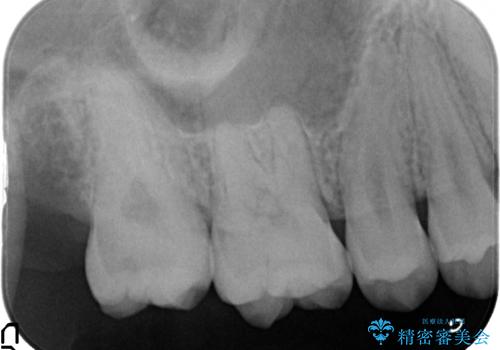

頬側に咬頭が一つ多い歯であったのと、歯肉に近い位置が虫歯になっていたため、被せものでしっかり覆う治療を行いました。